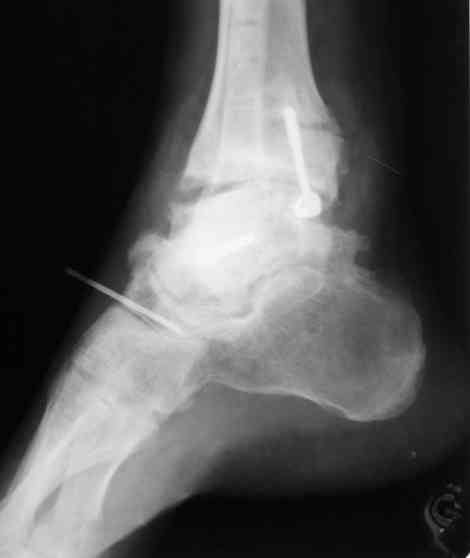

Interesting case

The ankle joint looks ruined. I wonder howcome is it as ruined after 2 days. I would open the joint( Some people would artroscope it) and judge the osteosynthes vs ankle fusion according to the ankle joint condition. The subtalar does not look injured, but if you feel there is a clinical

problem- CT it. Above all- when I see such an X-Ray I call the resident who ordered it and tell him that I would expect him first thing to reduce it on arrival since the soft tissue suffer and I hope that currently the p-nt is reduced to some extent at least.

Sorry- I revised it and the talus is fractured- take him to the theater at once and reduse it with Int Fix

The soft tissue will be a problem- Ex Fix will be better thn plaster

а основании двух видов ренгенограмм невозможно радикально решить о необходимости открытой репозиции или первичного артродеза.

Для оценки состояния нужны дополнительные исследования, например Canale или Broden ренгенограммы и Компьютерная томография.

При переломах тарана всегда имеется риск AVN, а классификация Hawkins поможет разобраться с предполагаемыми осложнениями.

Если в первом типе, когда перелом шейки без смещения, тогда AVN менее 10%, при втором типе когда имеется смещение и вывих тарана в субталарном сочленении меньше 40%, а при типе III когда смещение в голеностопном и субталарном суставах - около 90% и в типе IV, когда происходит полный вывих, риск AVN достигает 100%.